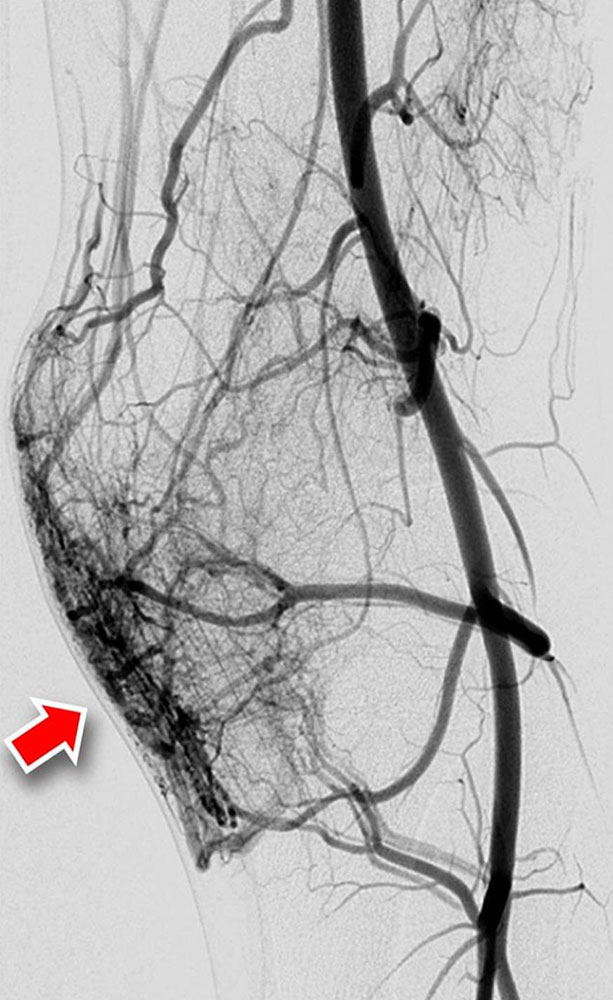

Fast-flow malformation (AVM and AVF): The exact anatomical morphology and the hemodynamics of a fast-flow vascular malformation can be very accurately analyzed with the use of DSA. The most important feature of a fast-flow vascular malformation is the immediate contrast filling of the draining veins via the nidus. Angiographically, fast-flow malformations can be categorized into four subtypes:

• A fine fistulous, net-like nidus is called type IIIa.

• In type IIIb the net-like nidus is dilated.

In advanced disease, the incoming and outgoing vessels are also increasingly tortuous and dilated. In some cases, flow-related aneurysms are formed.